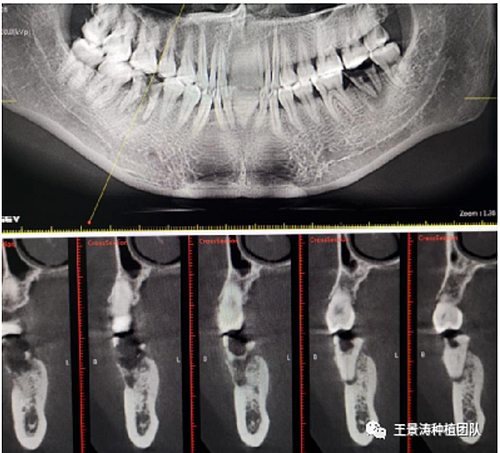

左側(cè)下頜第二磨牙及右側(cè)下頜第一磨牙同時(shí)即刻種植病例?;颊吣贻p女性,無系統(tǒng)性疾病。37及46殘冠及殘根,且46劈裂,無法冠修復(fù),必須拔除。37根尖慢性炎癥,大量肉芽組織存在,46根分叉較高,根分叉骨質(zhì)尚可。CBCT示:根尖骨質(zhì)至下牙槽神經(jīng)管距離可滿足種植體的初期穩(wěn)定性,遂考慮即刻種植,并在種植體周邊填入骨粉并覆蓋骨膜,雙側(cè)的種植體初期穩(wěn)定性相差無幾,但考慮到37根尖慢性炎癥較大,遂給予埋入式種植。

(3)根尖周無急性炎癥,慢性炎癥存在的情況下,需評估根尖骨質(zhì)可否使植體獲得良好的三維位置和初期穩(wěn)定性,對于上頜后牙區(qū)來說,如果可以經(jīng)過上頜竇內(nèi)提升實(shí)現(xiàn)雙層皮質(zhì)骨固位,獲得較好的穩(wěn)定性也可以考慮即刻種植;而下頜后牙區(qū)則需要評估根尖區(qū)域至下牙槽神經(jīng)管的距離,是否適合植入種植體;